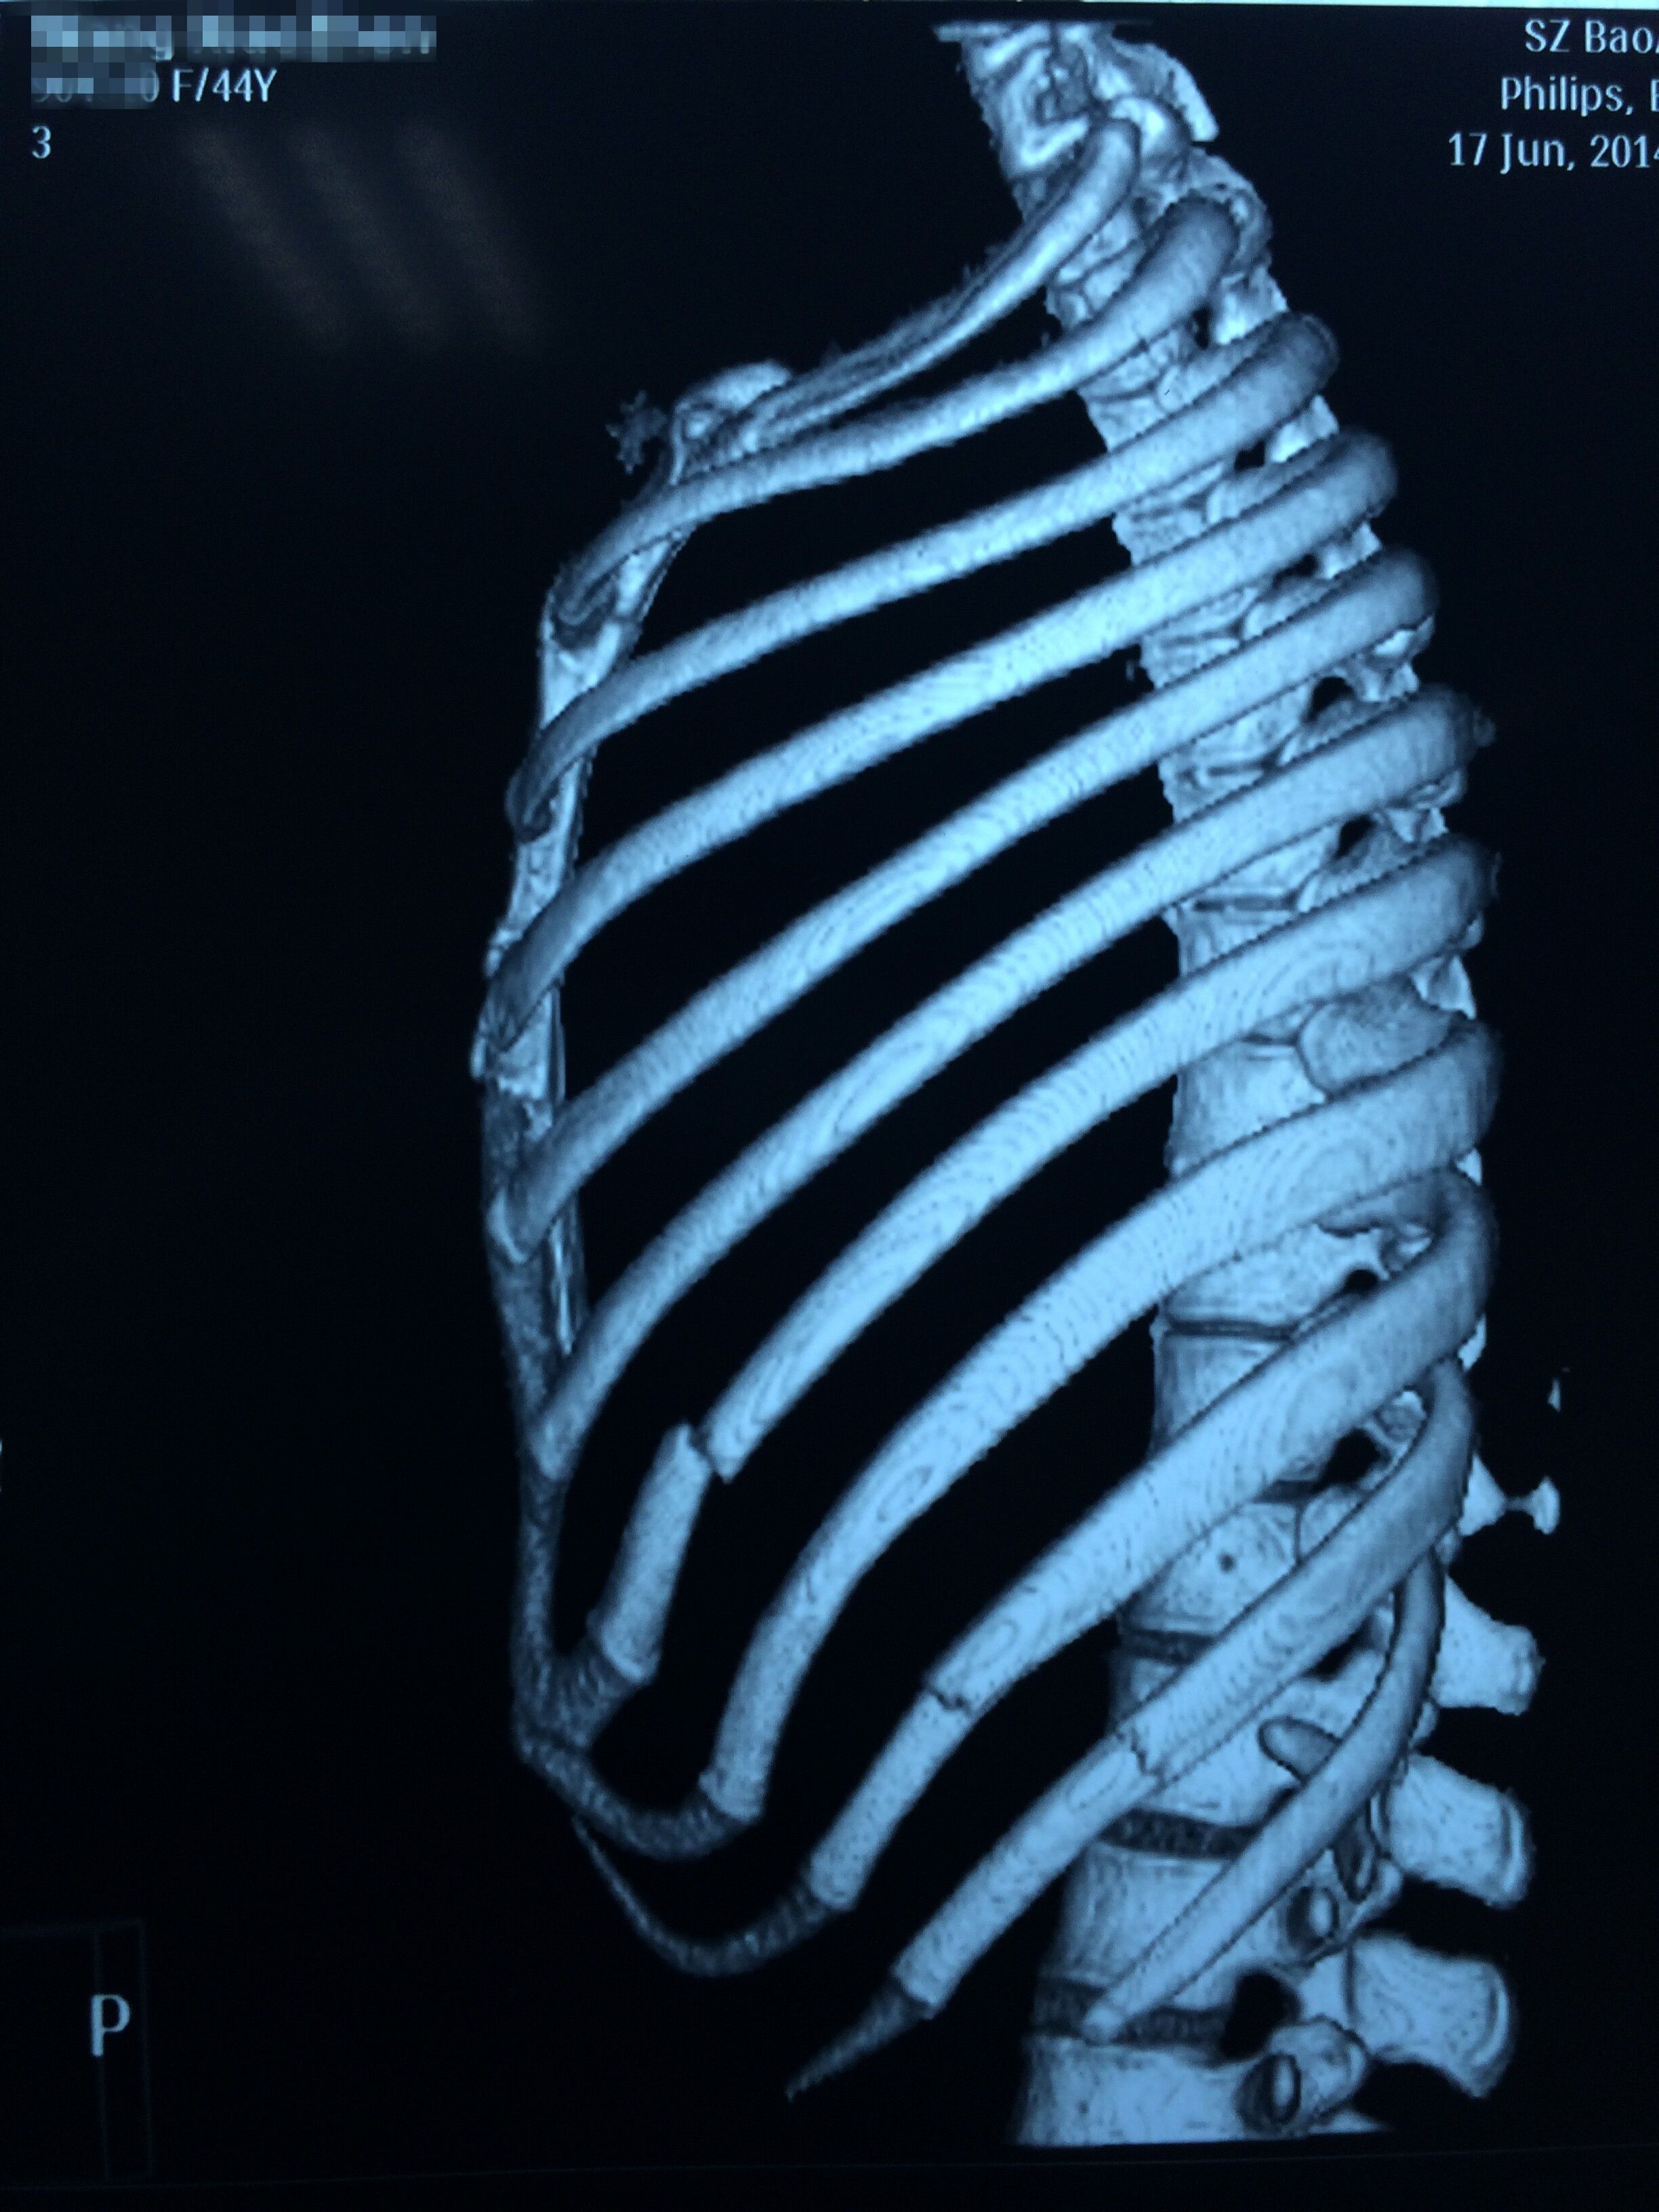

肋骨骨折什么症状 肋骨骨折主要的症状是胸痛,尤其是肋骨受伤的部位,局部的按压痛会非常的明显。 除了按压以外,病人如果在咳嗽、活动或者深呼吸的时候,也会明显的感觉到胸痛,这时候只有静止才能缓解。 如果骨折引起了肺破裂,引起了气胸,血胸 肋骨骨折是一种相当常见的损伤,包括或多或少严重的胸肋骨折 通常骨折只影响一根肋骨; 然而,在特别不幸的情况下,它会同时影响多个相邻的肋骨(多根肋骨骨折) 最常发生骨折的肋骨是位于肋骨中心的肋骨。 上肋骨(第一和第二)骨折通常发生在面部肋骨骨折 肋骨骨折とは、胸部を取り囲む骨にひびが入ったり骨が折れたりすることです。 肋骨骨折は重度の痛みを引き起こし、特に深呼吸したときに痛みがひどくなります。 通常は胸部X線検査が行われます。 痛み止めを投与され、肺の病気を予防する

肋骨骨折症状诊断 (一)、症状 1、在腋窝部的第6~9肋。 当肋骨本身有病变时,如原发性肿瘤或转移瘤等,在很轻的外力或没有外力作用下亦可发生肋骨骨折,称为病理性肋骨骨折。 2、肋骨骨折多发生在 3章:肋骨骨折の後遺症②神経症状 肋骨骨折で、 変形障害は残らなかったものの骨折した所に痛みやしびれが残ってしまう 場合もあります。 この場合、「神経症状」という症状で後遺障害等級が認定される場合があります。